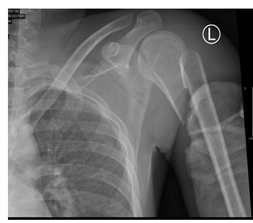

A 26-year-old male, soldier, involved in road traffic accident on 27th of August 2019 in the southern region of Saudi Arabia. The patient was transferred to the military hospital in the south and they stabilized him there and then transferred to our hospital on 29th of August 2019. The patient had multiple injuries: T3–T4 spinal fracture (Figure 1), left proximal humerus fracture (Figure 2), 8th & 9th rib fractures with multiple lacerations. He underwent for left open reduction and internal fixation of the proximal humerus by using Proximal Humerus Internal Locking System "PHILOS" plating on 03-Sep-2019 (Figure 3A & 3B). Also, the patient underwent spinal fixation for the fracture from T1 to T8on 05-Sep-2019 (Figure 3C). One month postoperatively, he started to have left big toe gangrene and vascular surgery was consulted. They recommended doing CT angiogram of the aortic arch and echocardiogram. CT showed that left pedicular screw of T6 and T8 appear lateral to the pedicle and the tip of the screws abutting the medial wall of the descending thoracic aorta at the posterior mediastinum but there is no obvious surrounding active haematoma or aortic thrombosis (Figure 4A & 4B). Pre-operative assessment and measurement were done and it was showed: Whole length supposed to be covered: 10cm, Proximal landing zone on the sagittal view: 2.67cm, Distal landing zone on the sagittal view: 1.83cm, Proximal axial: 2.14cm x 2.11cm, and distal axial: 1.92cm x 1.78cm.

Figure 2 X-ray of left shoulder showed displaced proximal humerus fracture.